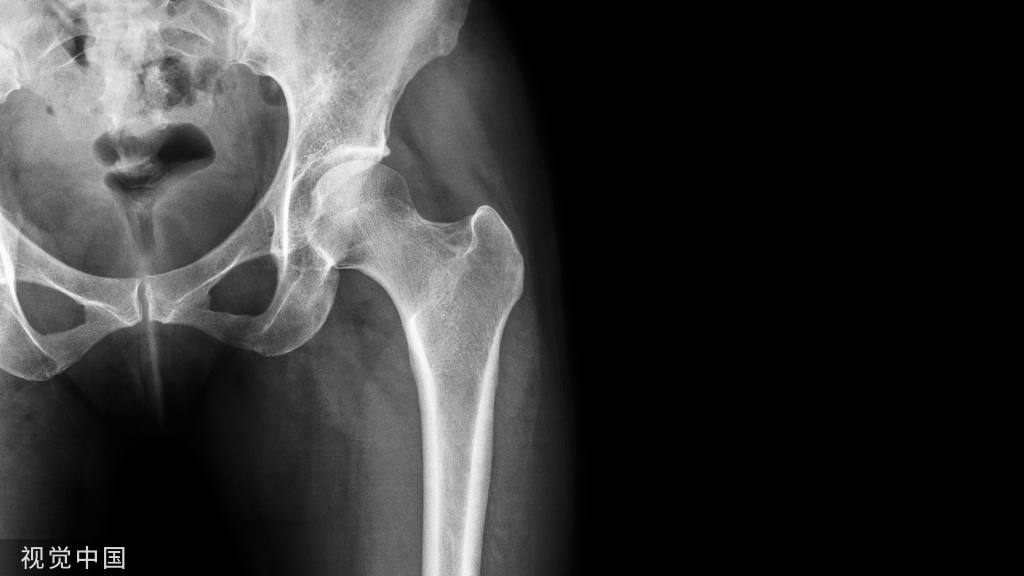

• 骨盆的前后位X线平片可以与对侧比较(对于发生在股骨转子间或股骨颈基底部的复杂股骨近端骨折特别有用)。

• 包括髋关节和膝关节在内,股骨全长前后位和侧位X线平片是必需的。

• 极少数情况下,CT有助于准确的确定转子下区域的骨折类型。例如,对于累及梨状肌隐窝的骨折,髓内钉的操作就需要特殊的技术。